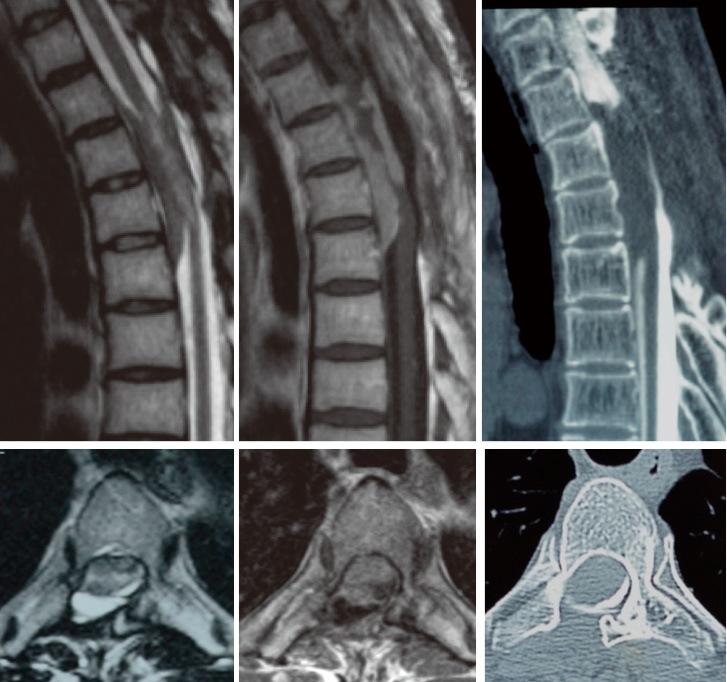

Meningioma is typically considered to be a benign tumor. Malignant transformation and metastasis of meningiomas are rare. Moreover, most meningiomas are intracranial, and there are few reports on intraspinal meningiomas. This report aimed to describe the clinical features and pathological findings of a case of malignant transformation and distant metastasis of intraspinal meningioma, with a review of the literature. A 44-year-old man with a bilateral lower limb paresis was diagnosed with an intradural extramedullary tumor of the thoracic spine. Primary tumor resection was performed, and the histological findings revealed atypical meningioma. The meningioma recurred 2 years after the primary surgery, and a second resection was performed, but only partial resection was possible because of decreased motor evoked potential. At age 48, the patient's lower limb weakness returned, and a third resection was performed, and the histological finding remained atypical meningioma. At age 54, the tumor increased and stereotactic irradiation was performed. At age 60, the patient was diagnosed with metastatic tumors of the rib, lumbar vertebra, cervical spine, and sacrum. Biopsy of the rib metastatic tumor was performed, and the histological findings revealed anaplastic meningioma. This case is the first report of an intraspinal meningioma that transformed from atypical to anaplastic meningioma with distant hematogenous metastasis.

脑膜瘤通常被认为是一种良性肿瘤。脑膜瘤的恶性转化和转移很少见。此外,大多数脑膜瘤位于颅内,关于脊髓内脑膜瘤的报道较少。本报告旨在描述一例脊髓内脑膜瘤恶性转化并远处转移的临床特征和病理结果,并对文献进行综述。一名44岁双侧下肢麻痹的男性被诊断为胸段脊柱硬脊膜外髓外肿瘤。进行了原发肿瘤切除术,组织学检查结果显示为非典型脑膜瘤。脑膜瘤在初次手术后2年复发,进行了二次切除,但由于运动诱发电位降低,只能进行部分切除。48岁时,患者下肢无力复发,进行了第三次切除,组织学检查结果仍为非典型脑膜瘤。54岁时,肿瘤增大,进行了立体定向放射治疗。60岁时,患者被诊断为肋骨、腰椎、颈椎和骶骨转移瘤。对肋骨转移瘤进行了活检,组织学检查结果显示为间变性脑膜瘤。该病例是首例脊髓内脑膜瘤从非典型转变为间变性脑膜瘤并发生远处血行转移的报道。